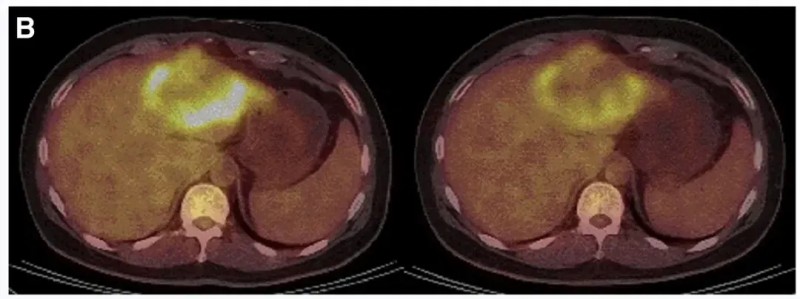

其中P9-2患者经PET/CT检查显示,肿瘤活动明显减弱、代谢活性显著降低(详见下图B)。

▲图源“Molecular Therapy”,版权归原作者所有,如无意中侵犯了知识产权,请联系我们删除